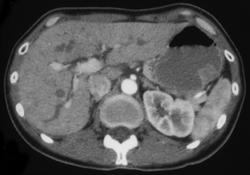

Subtle Gastric Cancer Nearly Missed By Food in the Stomach